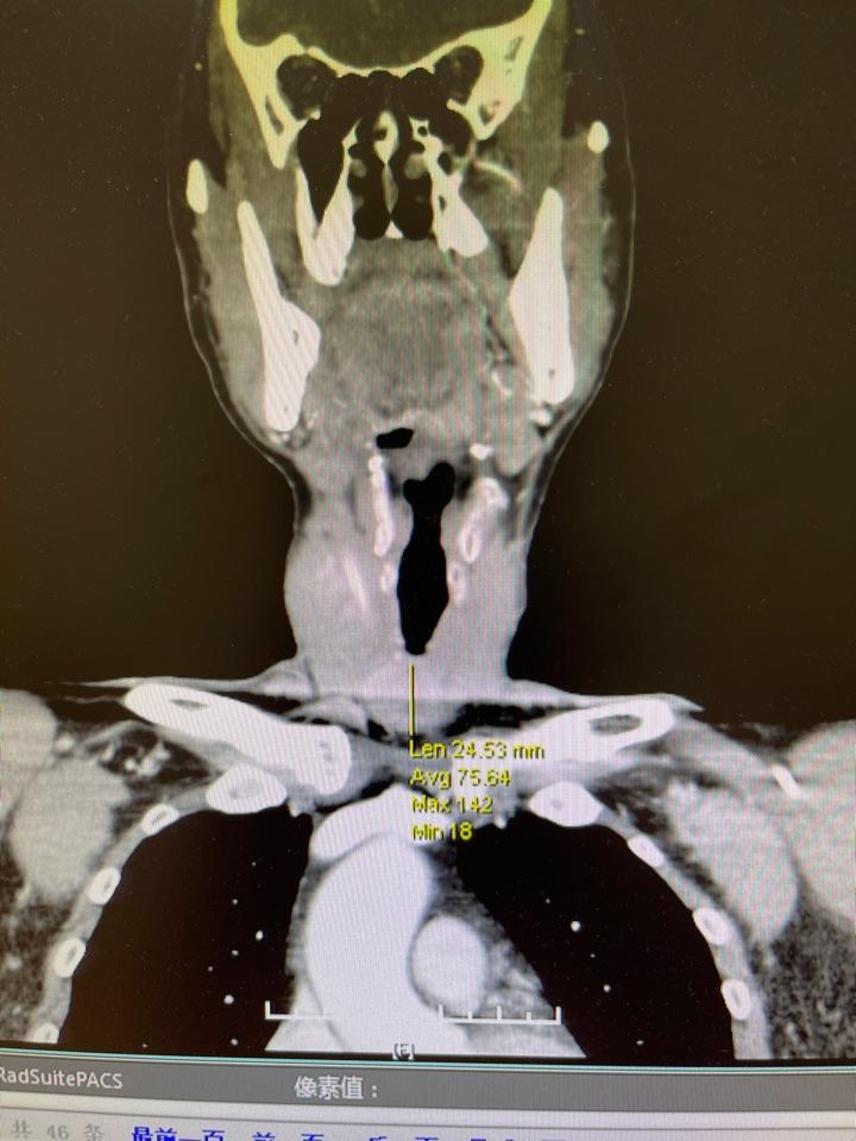

甲状腺ct平扫并增强,请大家分析 [病例帖]

图片尺寸4128x2322